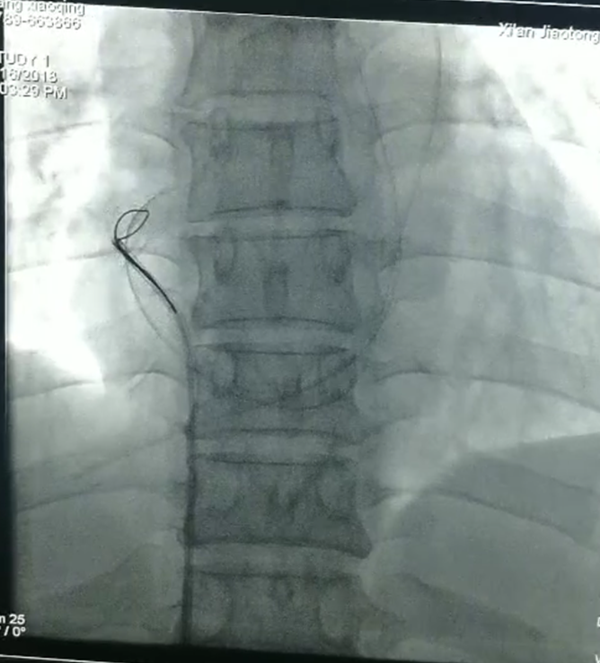

张开、收!

消毒铺巾以最快速度完成,穿刺,确认部位,放入网篮导丝,寻找断裂残端,小心翼翼拉出断裂的导管,一整套手法,董新教授前后用了仅十余分钟!断裂体内的导管直径约1.5mm,长约41mm,管子抓出来那一刻全体欢呼雀跃,掌声一片。